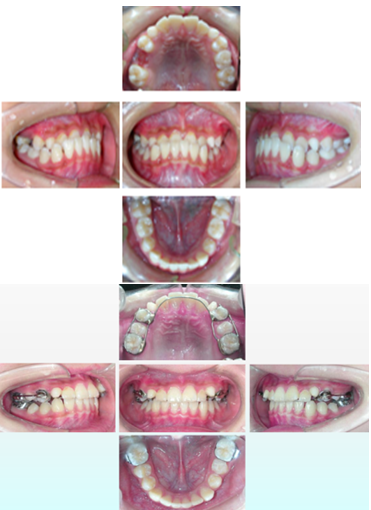

早期矫治前后合像对照:

固定矫治前后合像对照: